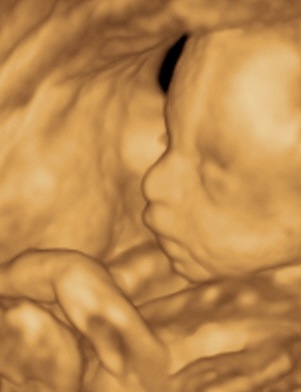

A 3D-s babafotok meg mindig lenyugoznek, nem birok betelni veluk. SZomoruan olvasom, hogy mennyi aprobb-nagyobb kellemetlensegetek van, de szerintem mindenki nagyon szuperul halad, ugyesek vagytok...le a kalappal foleg a dolgozok, vagy mar babasok elott! majd most teszek fel kepeket es is Azzurrarol, bar mar tobb, mint 5 hete keszultek, de ujabbak mar nem lesznek, es mivel kimaradtam abban az idoszakban, most potolom. Az tuti, hogy ezentul mindenkinek javasolni fogom a 4D-t ilyen koran is (22+1 hetesen voltunk), mert bar csimota ducibb volt az atlagnal es mar akkor volt rajta jo adagnyi izom (ez is a napi 1 l tej

), de egy sovanyabb baba is csodaszep szerintem...mindent el lehet mondani, csak azt nem, hogy csontkollekciok lennenek. Osszessegeben ugy nez ki, hogy ram hasonlit, de a szemoldokcsontja es a szaja az egy az egyben a parome...szerencsere...neki az sokkal szebb...remelem, haj-ugyben is ra ut majd